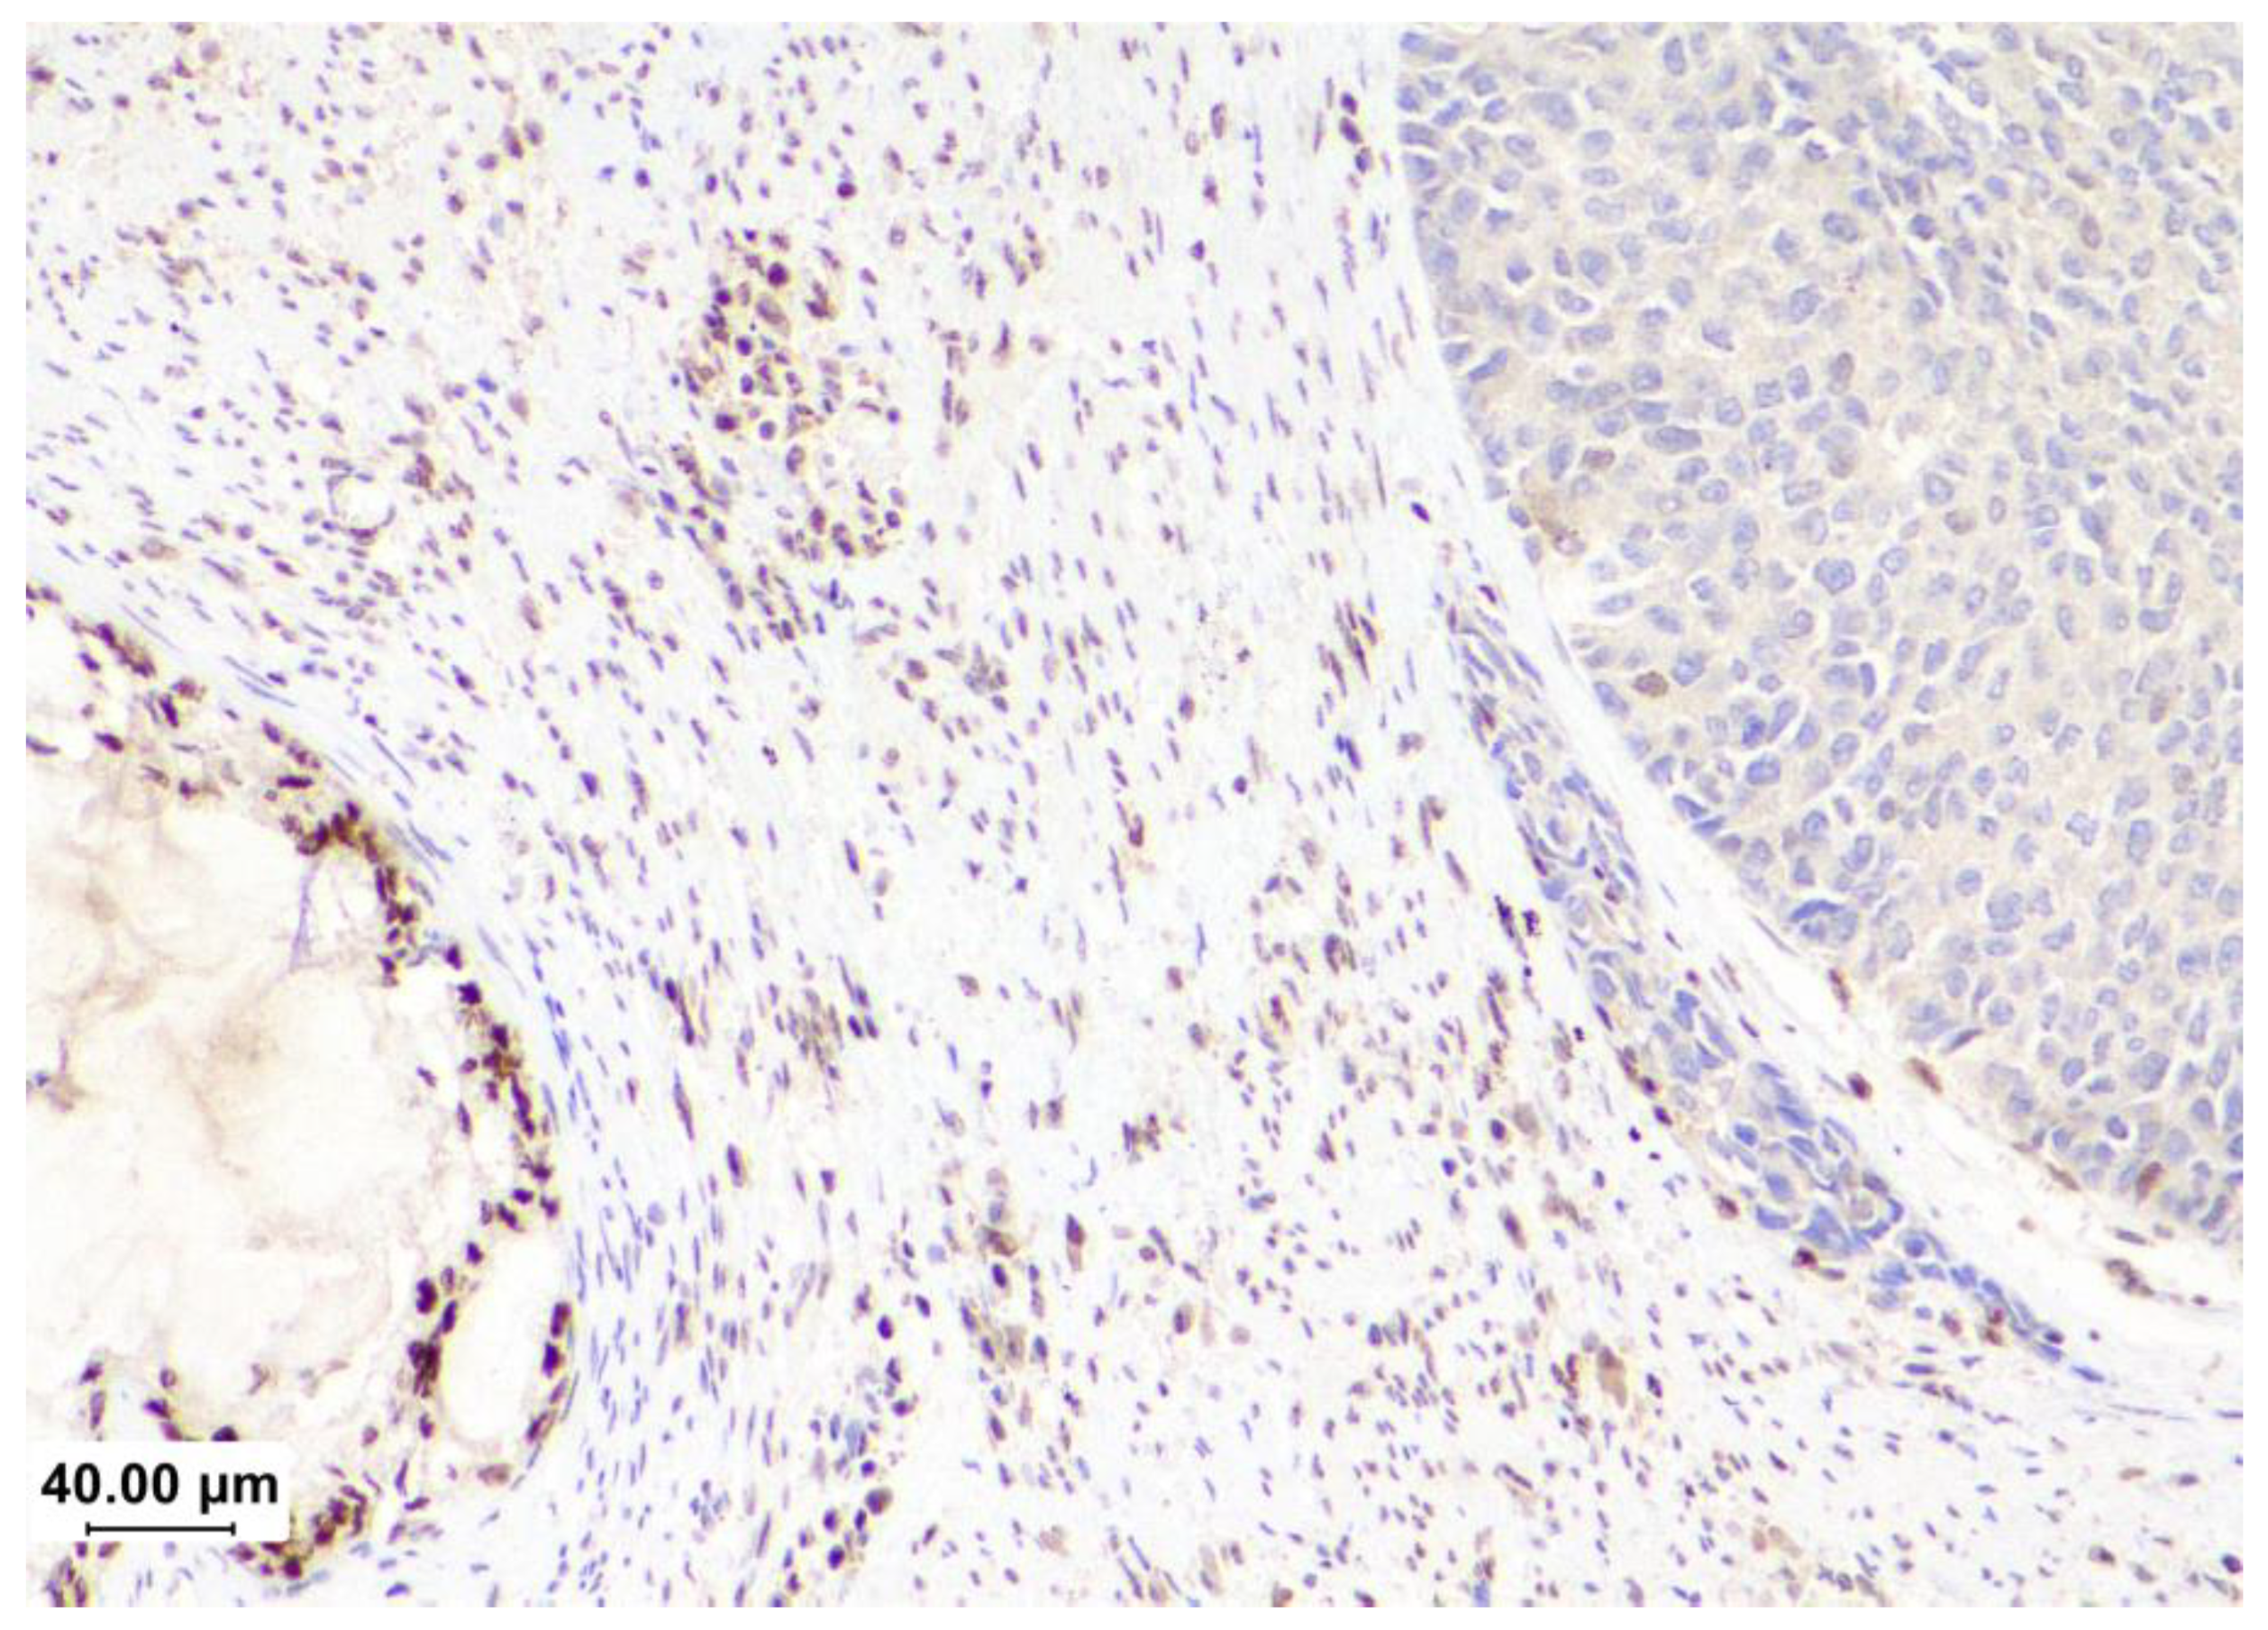

- Addante F, d’Amati A, Santoro A, et al.: Mismatch Repair Deficiency as a Predictive and Prognostic Biomarker in Endometrial Cancer: A Review on Immunohistochemistry Staining Patterns and Clinical Implications. Int J Mol Sci. 2024, 25. [CrossRef]

- Ramchander NC, Ryan NAJ, Walker TDJ, et al.: Distinct Immunological Landscapes Characterize Inherited and Sporadic Mismatch Repair Deficient Endometrial Cancer. Front Immunol. 2019, 10:3023. [CrossRef]

- Chavez JA, Wei L, Suarez AA, Parwani AV, Li Z: Clinicopathologic characteristics, tumor infiltrating lymphocytes and programed cell death ligand-1 expression in 162 endometrial carcinomas with deficient mismatch repair function. Int J Gynecol Cancer. 2019, 29:113-118. [CrossRef]